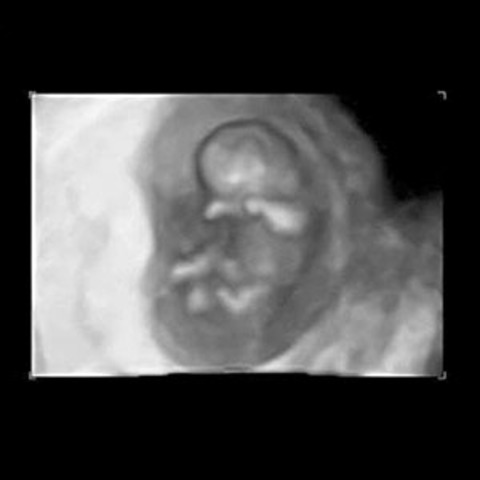

• Prenatal - Fetus

Prenatal - Fetus

http://www.parents.com/pregnancy/week-by-week/10/your-growing-baby-week-10/ 10 weeks (8 weeks after conception) The baby has officially graduated from an embryo to a fetus. At this time the fetus measures approximately 1 inch. The eyes, nose, lips, teeth, and tongue are beginning to take shape. The vital organs, such as the kidney, liver, intestines and brain, are starting to function. The fetus is able to make movements inside the uterus, but it cannot yet be felt by the mother.